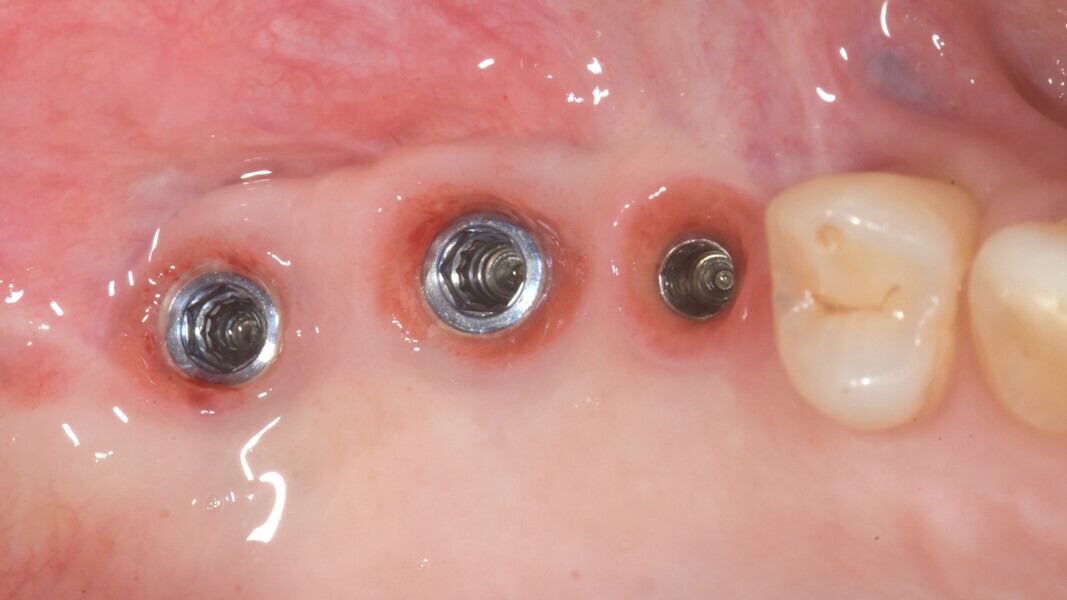

Subsequently, the surgical guide was placed and fixed in the planned position, the implant sites were prepared with progressive dedicated drills and three conical implants (T3, ZimVie) were placed in sites #15, 16 and 17 according to the prosthetically guided plan obtained from the guided surgery software (Figs. 29, 30a-c, 31a & b). The implants were covered to allow for proper osseointegration, and first intention closure was performed (Figs. 32a & b). After implant placement, a dental panoramic tomogram was taken (Fig. 33).

After three months, the implants were exposed through an apically positioned flap to increase the amount of keratinised tissue on the vestibular side of the implants and to realign the mucogingival junction, previously shifted towards the palate. Flared healing screws were placed to promote proper transmucosal healing. After one month, single ceramic crowns were placed for the first functional loading and temporary restoration while waiting for complete bone maturation (Fig. 34). After six months, the crowns were replaced with zirconia crowns for the final functional loading and the definitive restoration (Figs. 35–38). Clinical and radiographic follow-ups at the first functional loading, at six months, 12 months and 24 months showed the health of the peri-implant tissue and the maintenance of peri-implant bone levels (Figs. 39a-d).